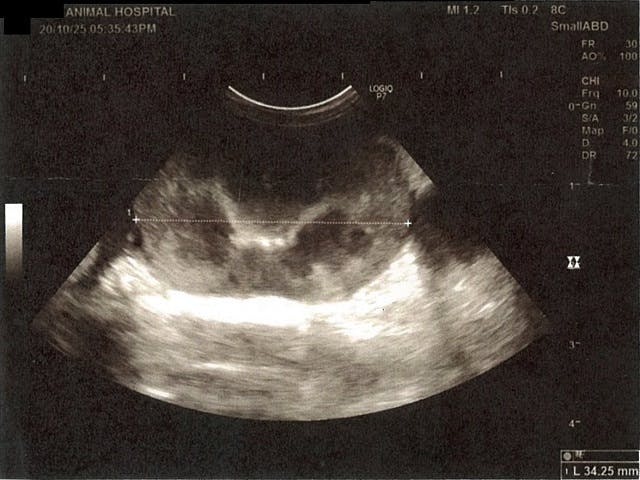

《心臓周りの胸部以外の全ての腹部で腹水がみられるとの診断です》

膀胱周りに腹水が確認できるエコー写真

膵臓周りに腹水が確認できるエコー写真